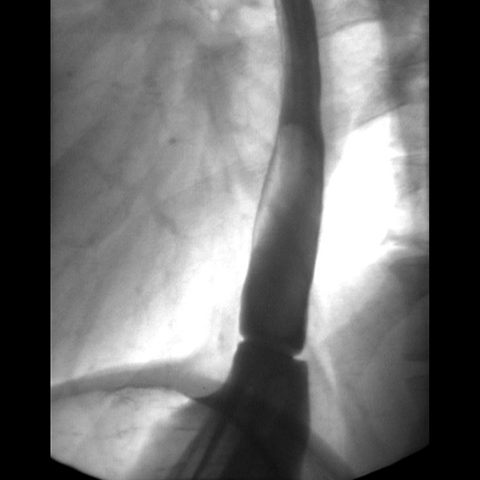

Hiatal Hernia, Barium Study [1 of 2]